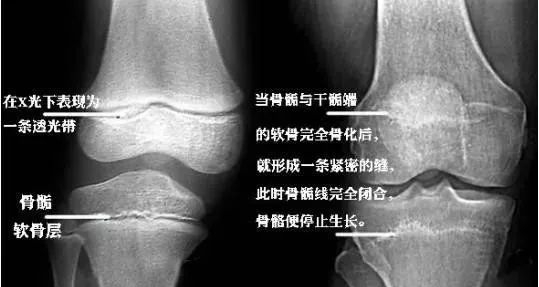

儿童骨骺损伤影像诊断

骨骺闭合之前怎么长高石家庄港大妇女儿童医院蔡西萍主任解答

孩子长高有3个黄金期,矮小门诊教授:骨骺线未闭合前,有机会!

男孩开始长喉结或变声,意味着骨骺线接近闭合了,女孩在月经初潮来后

原创14岁男孩身高153检查后医生骨骺线已闭合最多还能长23㎝